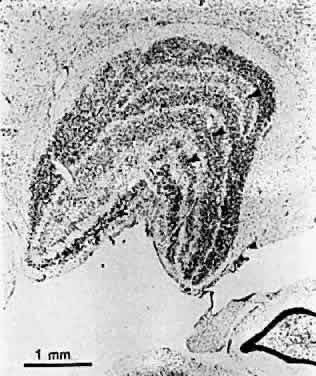

Hubel and Wiesel's first studies of monocularly lid-sutured kittens revealed unexpectedly that cell bodies in the lateral geniculate nucleus (LGN) that received input from the deprived eye were considerably smaller than those of cells in adjacent laminae the input of which came from the nondeprived eye (Fig. 16). This observation has been confirmed by many investigators in a number of species, including humans, and for every form of unilateral visual deprivation.72,80 It is generally believed to be a reflection of the decreased extent of the geniculocortical cells' terminal axonal branches in the visual cortex (corresponding to contracted cortical dominance columns). Reverse lid suturing of the normal eye after an initial period of monocular deprivation in the monkey has been shown to reverse the cortical ocular dominance shift without reversing the LGN changes.81 This suggests that there is some degree of independence between the two levels and greater or more prolonged plasticity in the cortex.

Fig. 16. Coronal section through the right lateral geniculate nucleus of the same monkey shown in Figure 15. Atrophy in the layers receiving input from the deprived eye is indicated by arrows. (Wiesel TN. Postnatal development of the visual cortex and the influence of environment. Nature 1982;299:583.)

Cell shrinkage due to unilateral visual deprivation occurs to a significantly lesser extent in the monocular segment of the LGN (which receives input from the monocular temporal crescent of the contralateral eye's visual field), indicating that interaction between cells driven by the normal and deprived eyes in the binocular portion of the nucleus contributes to (but does not entirely account for) the phenomenon.82 Another abnormality that has been found to be largely confined to the binocular segment of the LGN in cats following total monocular deprivation is absence of Y cells, which are the subset of neurons (believed to correspond to the magnocellular pathway in primates) that normally processes the low spatial frequency information that is basic to overall form vision.83 Strabismus and optic blur from atropinization seem not to affect the Y-cell population but may disturb the ability of high frequency sensitive X cells (corresponding to primate parvocellular neurons) in the LGN to resolve fine detail.84